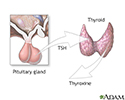

- Thyroid-stimulating hormone (TSH) -- stimulates the thyroid gland to release hormones that affect the body's metabolism

In hypopituitarism, there is a lack of one or more pituitary hormones. Lack of a hormone leads to loss of function in the gland or organ the hormone regulates. For example, lack of TSH leads to loss of normal function of the thyroid gland.

Pituitary and TSH - illustration

Pituitary and TSH

illustration